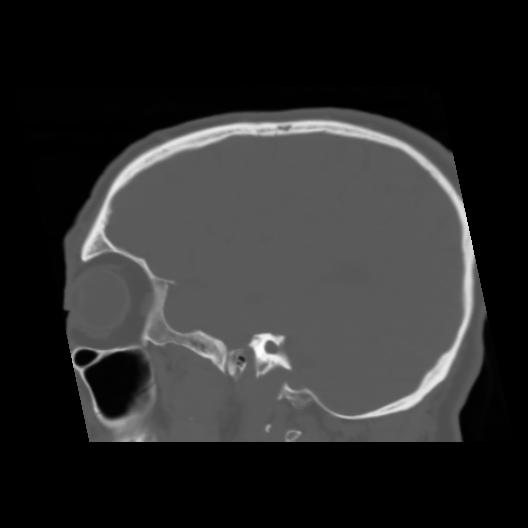

6 CEREBRO,,Sagittal,3.000,CEREBRO,Sagittal,